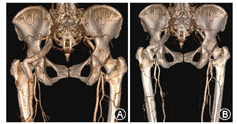

患者女,69岁,因"发现左臀部搏动性肿块1年"住院治疗,自诉有数年活动后下肢不适症状。查体:左臀部扪及搏动性包块,大小约5 cm×5 cm,轻压痛,左侧股动脉搏动弱,腘动脉搏动尚可,足背动脉未及,右侧正常。下肢CT血管造影(CTA)见髂内动脉发出粗大分支至左下肢,伴瘤样扩张,同侧股动脉纤细(图1)。术前诊断为永存坐骨动脉合并坐骨动脉瘤形成。于局麻下行下肢动脉造影,测量瘤体长度95 mm,近端直径13 mm,远端直径11 mm(图2A),遂选用戈尔公司viabahn支架13 mm×13 mm×100 mm一枚及美敦力公司Endurant支架16 mm×16 mm×93 mm一枚,支架重叠约5 cm,术后瘤体不显影,无内漏(图2B)。术后左臀部搏动性肿物消失,疼痛症状明显好转。术后随访至29个月,CTA复查支架无狭窄、无变形,下肢血流通畅(图3A)。后患者自行停用抗血小板药物,随访至术后46个月,支架完全闭塞(图3B),但患者未诉下肢缺血症状,决定继续随访观察。

注:A图:术后29个月支架通畅,形态良好;B图:术后46个月支架闭塞

由于坐骨动脉瘤极其罕见,故没有与之匹配的商品化产品。本个案术中测量瘤体近端锚定区直径13 mm,远端锚定区直径11 mm,所以各选择放大率(oversize)约10%的支架。选择两枚支架套叠,一是因为没有合适锥形的覆膜支架;二是考虑到髋关节运动、坐姿及坐骨动脉瘤的解剖位置,Viabahn支架具有高顺应性及高通畅率的同时,支撑力不足恐怕会影响远期通畅率,而Endurant髂支支架有较强的径向支撑力,应用于近端可以减少支架变形、移位及内漏的发生率。该患者术后29个月随访CTA发现支架通畅无变形,证实了支架植入短期疗效的可靠性。然而患者自行停用抗血小板药物,随访至术后46个月发现支架已经完全闭塞,但支架形态较术后29个月无明显变化,动脉瘤大小亦未发生改变。该患者未诉明显下肢缺血症状,因而决定暂不特殊处理,继续调脂及抗血小板等药物治疗,继续随访评估其动脉瘤大小变化、下肢缺血症状及支架形态学改变。Aziz等[5]报道约31%~63%的永存性坐骨动脉患者有下肢缺血症状,而本例患者未发生下肢缺血,其原因可能是支架植入为下肢动脉侧支循环争取了足够时间,且预防了附壁血栓脱落引起下肢动脉栓塞。